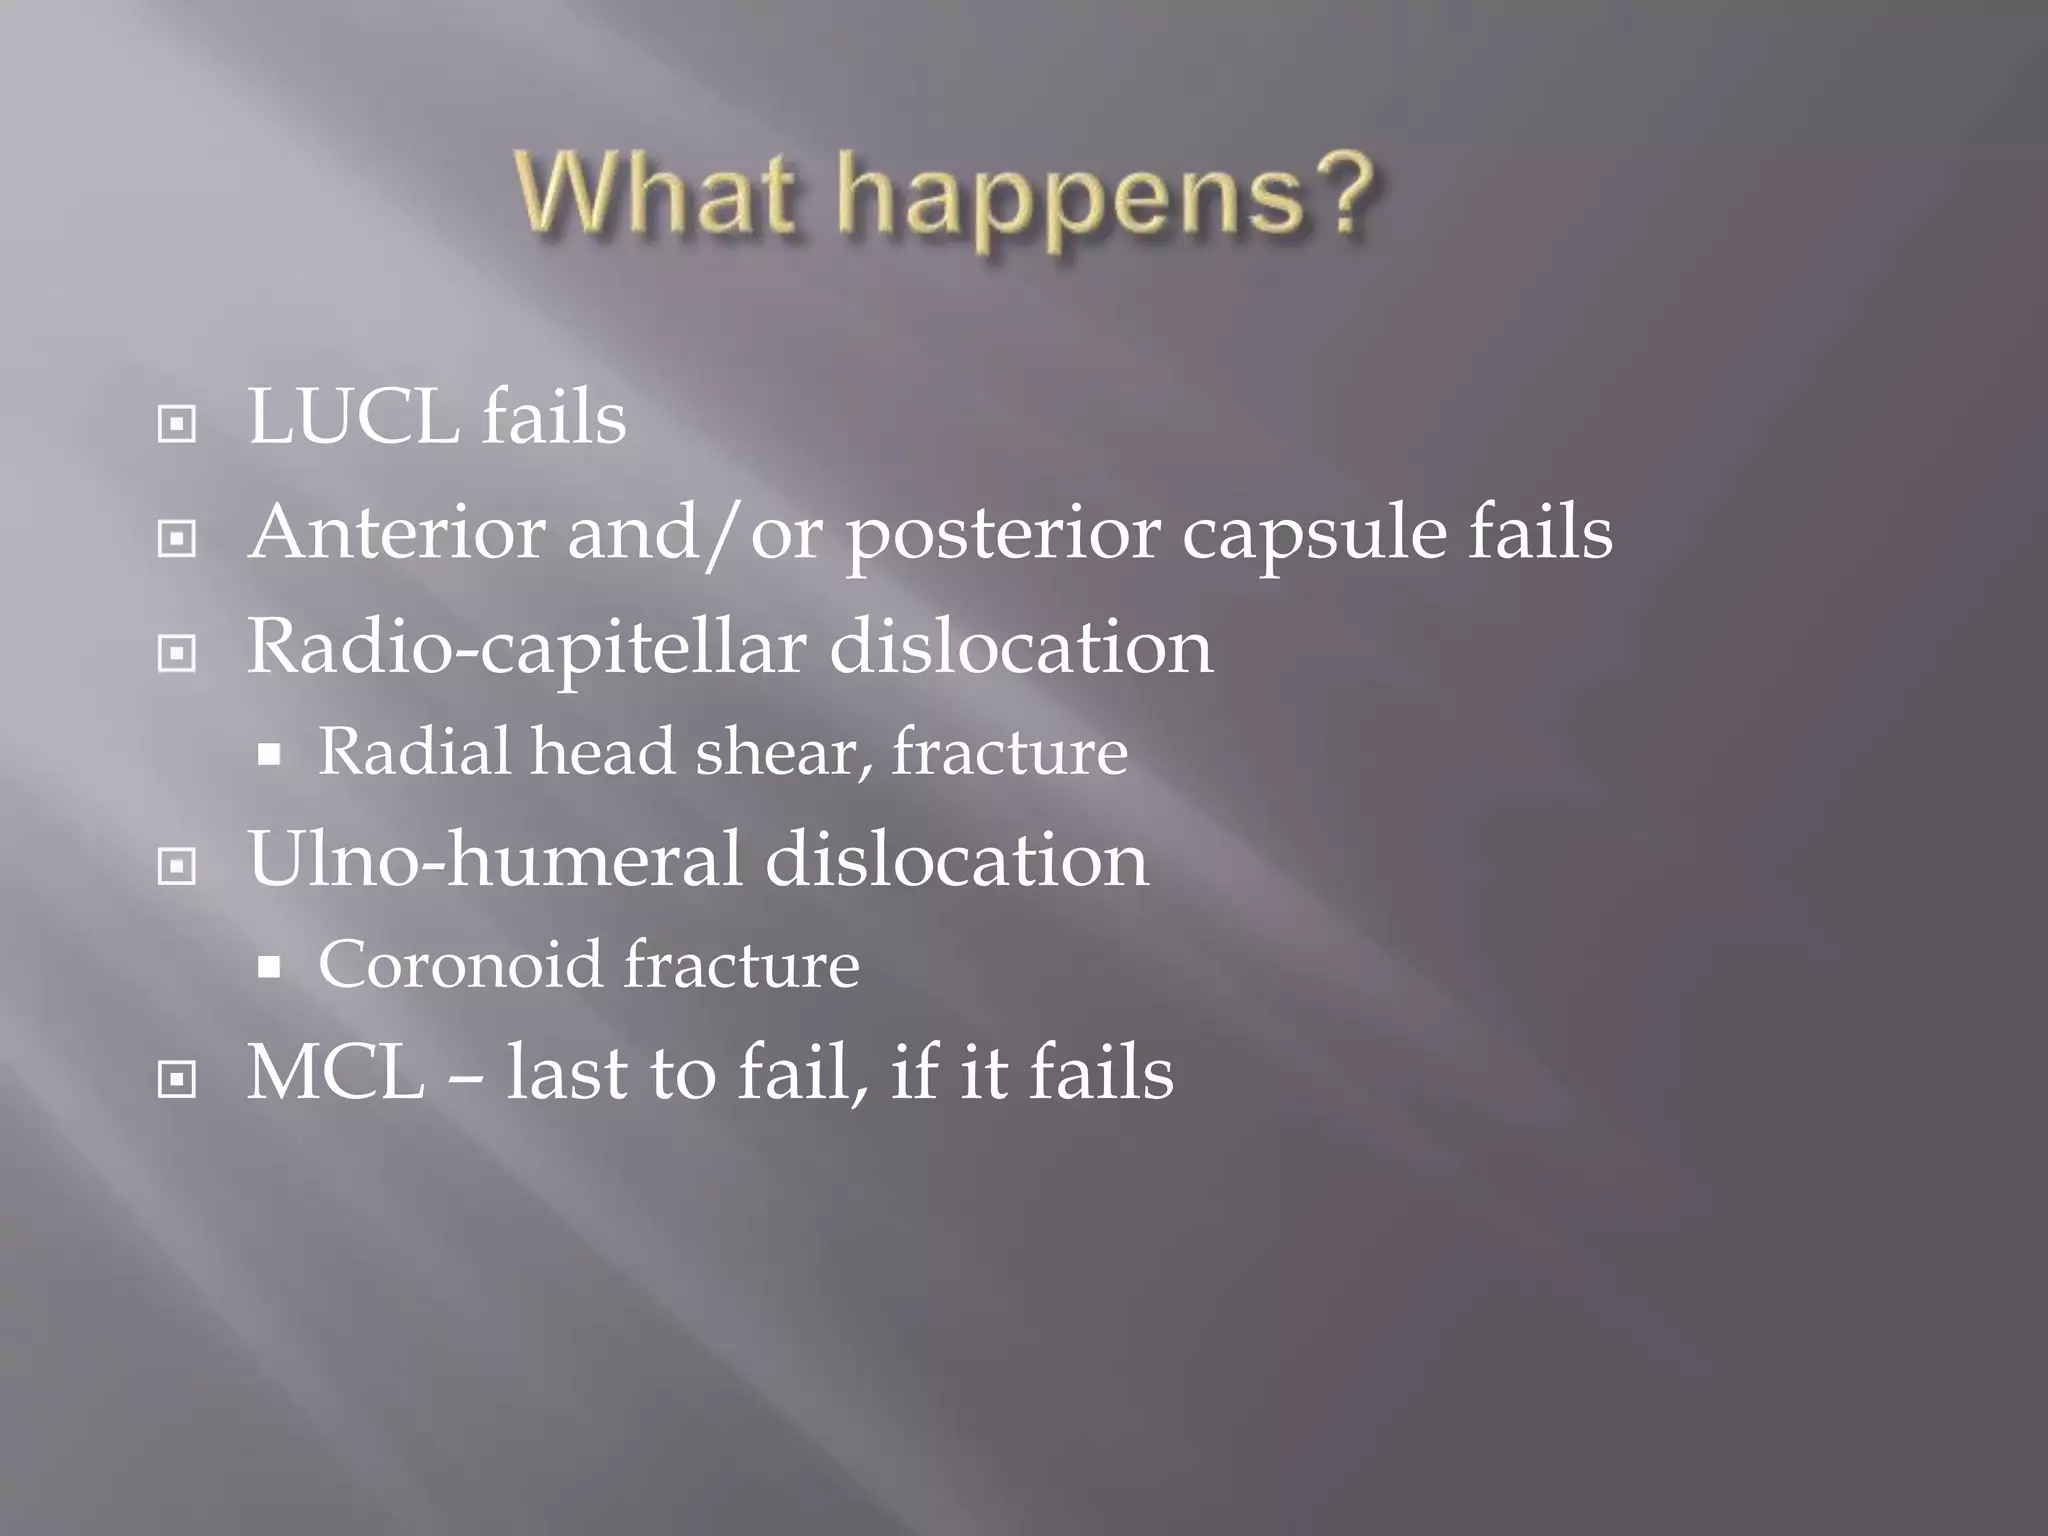

This document discusses the terrible triad injury of the elbow, which involves fractures of the radial head, coronoid process, and posterolateral dislocation. It notes the poor outcomes associated with this injury like stiffness, instability, and hardware failure. The document outlines the relevant anatomy of the medial collateral ligament and lateral uncular collateral ligament. It describes the mechanism of injury, known as the fall on an outstretched hand, and how the ligaments and capsule fail in this injury. Diagnostic imaging and classification of radial head and coronoid fractures are covered. Treatment options including observation, resection, open reduction internal fixation, and replacement are presented. Surgical approaches and techniques are also outlined.